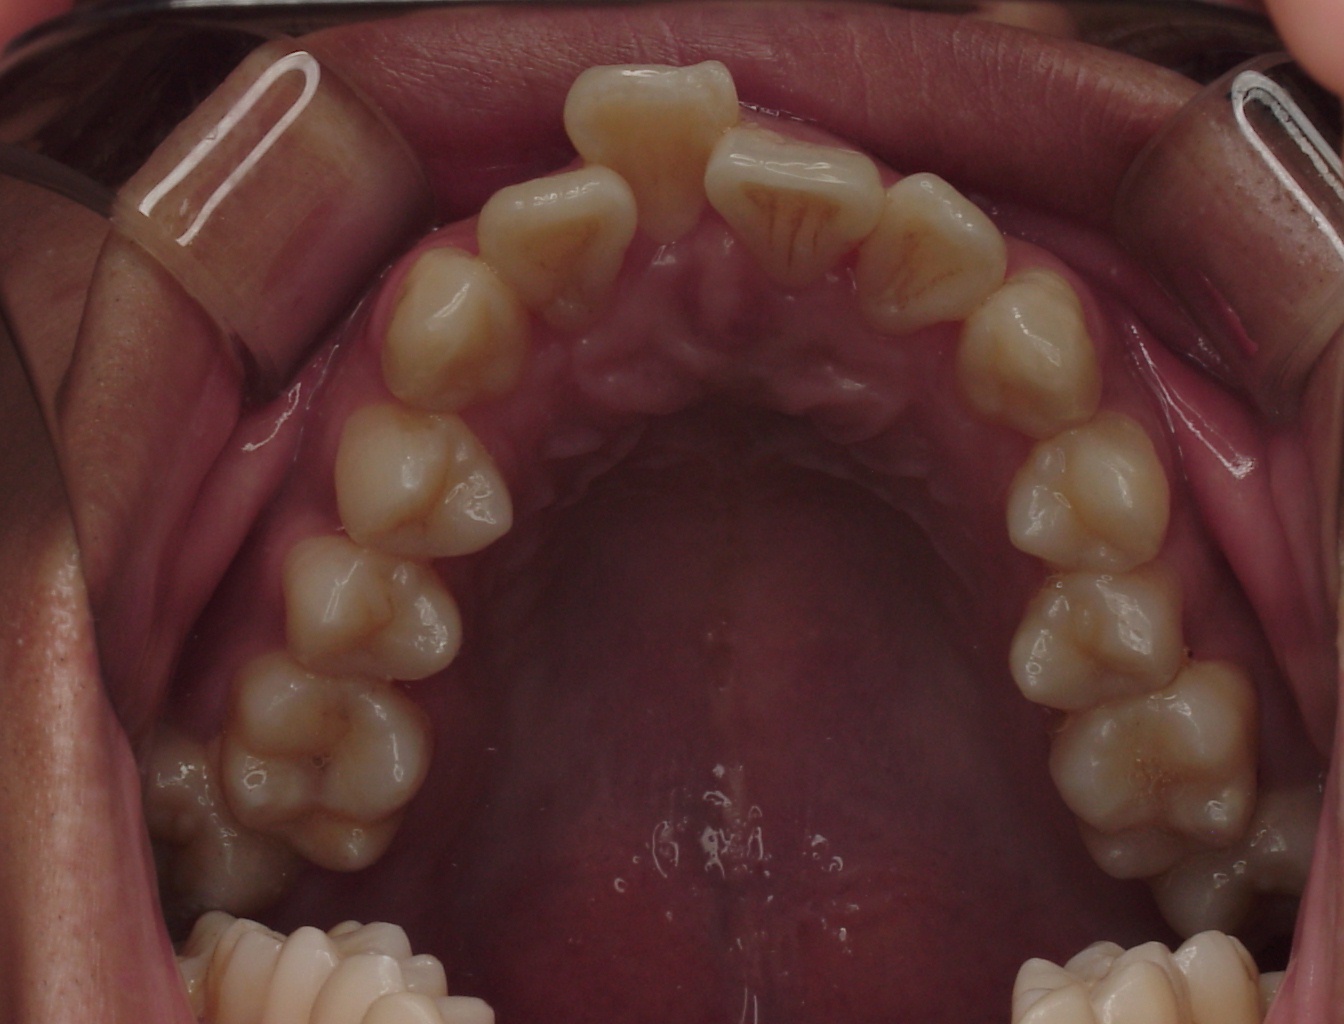

치료 전 사진입니다.